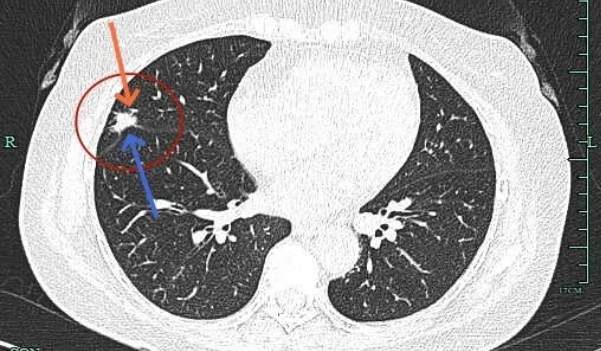

病灶大部分实性,边缘细毛刺与少许磨玻璃成分。

感觉整体病灶有膨胀性,边缘有毛刺征,灶内密度不是太致密。